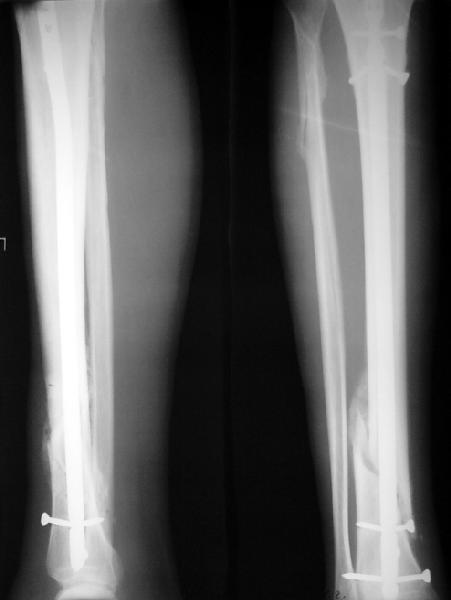

Ok. А также и следующий, в 3 месяца.

Это наглядная демонстрация возможности ранней полной нагрузки при нестабильном по оси повреждении, причем не в самых благоприятных механических условиях - при плохом сопоставлении, со слабым фиксатором.